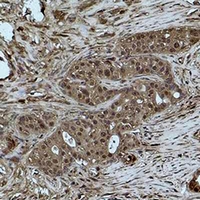

IHC (Immunohiostchemistry)

(Immunohistochemical analysis of Histone H3 (MonoMethyl K27) staining in human breast cancer formalin fixed paraffin embedded tissue section. The section was pre-treated using heat mediated antigen retrieval with sodium citrate buffer (pH 6.0). The section was then incubated with the antibody at room temperature and detected using an HRP conjugated compact polymer system. DAB was used as the chromogen. The section was then counterstained with haematoxylin and mounted with DPX.)